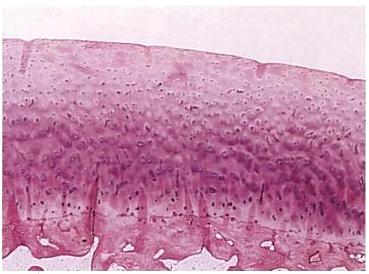

Fig. 13. Imagine microscopica a cartilajului articular sanatos.

Scopul acestei tehnici este de a stimula maduva osoasa, care la randul sau va genera un raspuns vascular stereotip la aceasta interventie. Se obtine astfel un raspuns biologic care se divide in 3 faze distincte: necroza, inflamatie, vindecare. Necroza incepe imediat dupa leziune si este caracterizata cu diferite stadii ale tesutului mort in functie de severitatea traumei si de fluxul adecvat de sange. Necroza este mai evidenta la marginile defectului condral. Faza inflamatorie este mediata de vascularitatea locala. O hiperemie reactiva si o crestere a permeabilitatii capilare, duce la transudatie si exudatie celulara care formeaza o retea densa de fibrina la locul leziunii. Aceasta retea este bogata in celule inflamatorii si este propice pentru divizarea celulara si vindecare. Deasemenea reteaua se organizeaza ca un lipici primitiv. Faza vindecarii incepe cand reteaua de fibrina este invadata de neovascularizatie. Incepe apoi o cascada de evenimente. Celulele inflamatorii modulate in fibroblast, pierd tesut granulomatos, iar in cele din urma se maturizeaza intr-o matrice de reparatie fibroasa rezultand cicatricea. Procesul de remodelare incearca sa recreeze anatomia normala.[51]

Raspunsul corpului la o rana exclusiv cartilaginoasa urmeaza o cale putin diferita. Motivul acestei diferente este ca cu o rana exclusiv cartilaginoasa, discul subcondral nu este penetrat. In timp ce cartilajul sufera aceeasi faza de necroza ca orice tesut din organism, faza inflamatorie e aproape complet absenta. Procesele de transudatie, exudatie, hematom si formarea sunt absente. Astfel nu exista cheagul de fibrina care sa asigure un esafod pentru reparatii. Fara celule reparatorii noi, sarcina de a repara cade pe condrocitele existente. Pe de alta parte, in cazul in care vatamarea se extinde prin intermediul zonei calcifiate la osul subcondral, toate cele trei faze de reparatie sunt stimulate.

Intreaga densitate articulara condrala afectata in urma leziunii sau forajului plina cu sange se organizeaza rapid intr-un cheag. Celulele sanguine nediferentiate- elemente ale maduvei osoase, si trombocite toate combina la deficienta. Celulele mezenchimale nediferentiate pot aparea din maduva osoasa, panus, membrana sinoviala sau zona superficiala a cartilajului articular. Acest tesut este capabil de diferentiere in mai multe tipuri de tesut fibros, inclusiv tesut osos si membrana sinoviala. In functie de locatia anatomica si de conditiile preexistente, aceste celule pot fi capabile sa se transforme in cartilaj hialin.